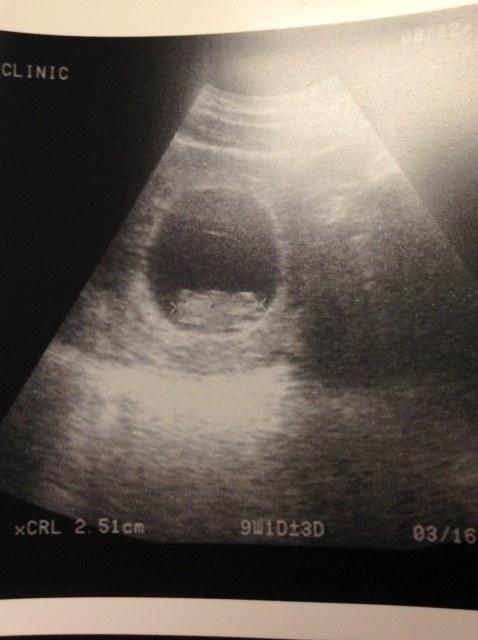

Here is a picture of our little bean from our appointment 2 weeks ago (I forgot to share last week).